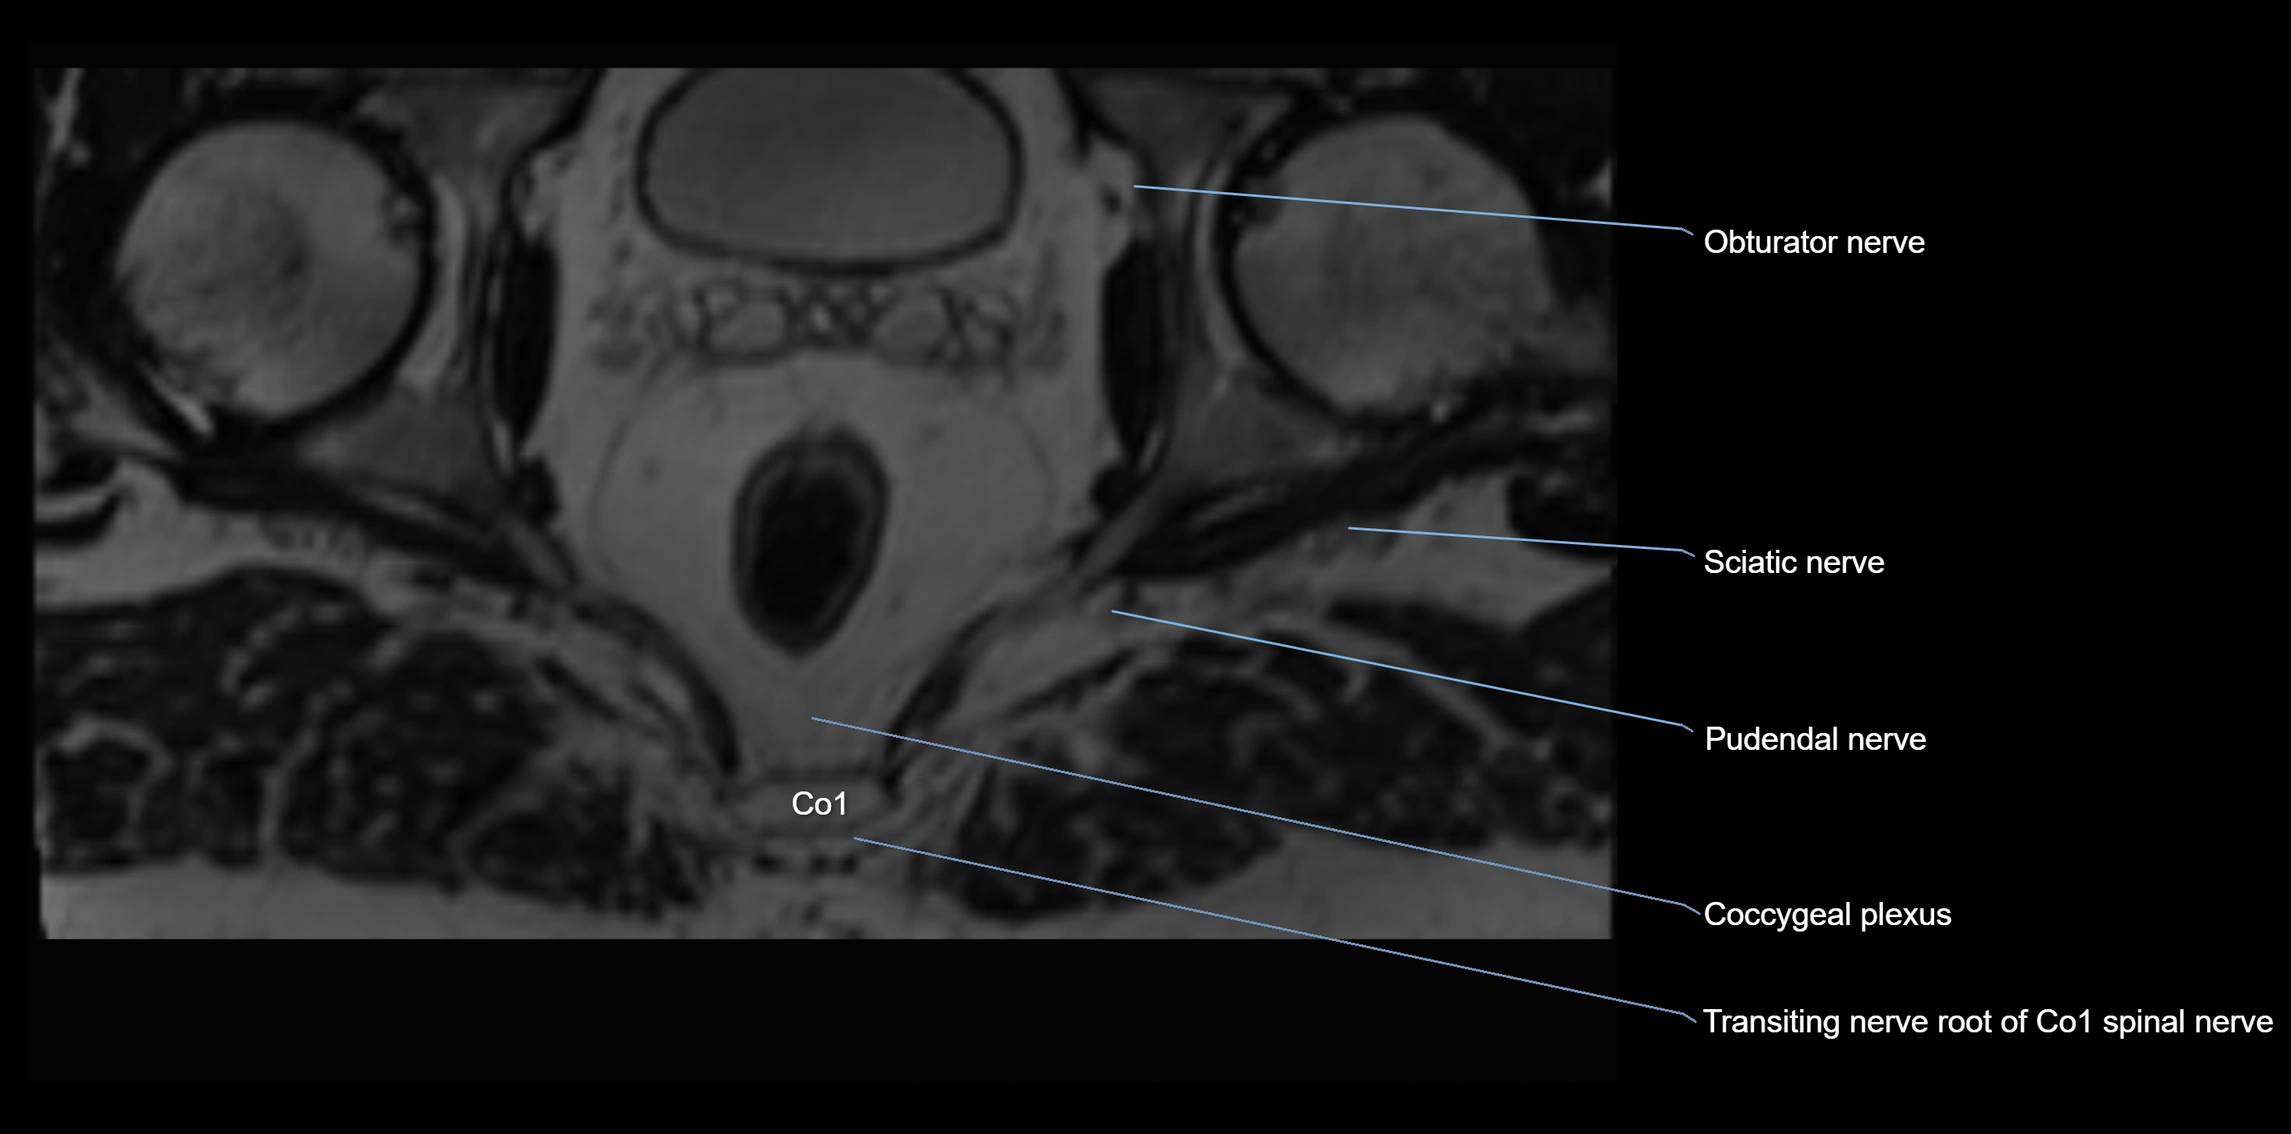

The anococcygeal nerve is a small sensory nerve derived from the coccygeal plexus, which itself is formed by the ventral rami of S4, S5, and the coccygeal nerve (Co1). Although tiny, this nerve plays an important role in supplying the skin of the coccyx and the area between the anus and coccyx. It passes through the sacrotuberous ligament and runs in the midline behind the coccyx.

• Arises from the coccygeal plexus, formed by ventral rami of S4, S5, and Co1

MRI image

image